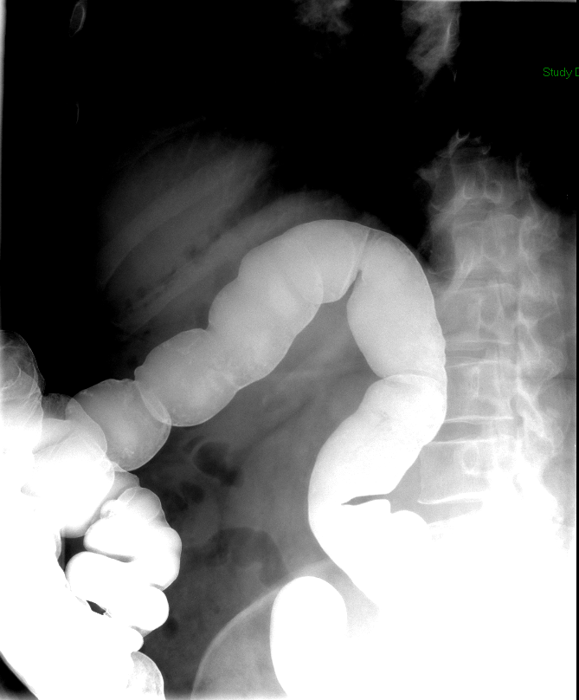

- The technologist will obtain radiographs at 30, 45, and 60 minutes after the initial administration of barium. If the column of contrast material has not reached the large bowel on the 60 minute film, the technologist will obtain images every 30 minutes until contrast can been seen in the cecum

(key image 3)

(key image 4)

(key image 5).

- Obtain images of the terminal ileum and the ileocecal valve filled with contrast material

(key image 6)

(key image 7)

(key image 8)

(key image 9)

(key image 10).

- Obtain spot images of the remainder of the small bowel

(key image 11)

(key image 12)

(key image 13)

(key image 14).

- Obtain images of all four quadrants. Use the compression paddle to separate loops of small bowel from each other.